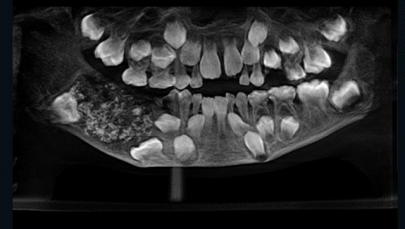

526 teeth found in Indian boy's mouth

Boy suffers from a rare condition known as ‘compound composite odontoma'